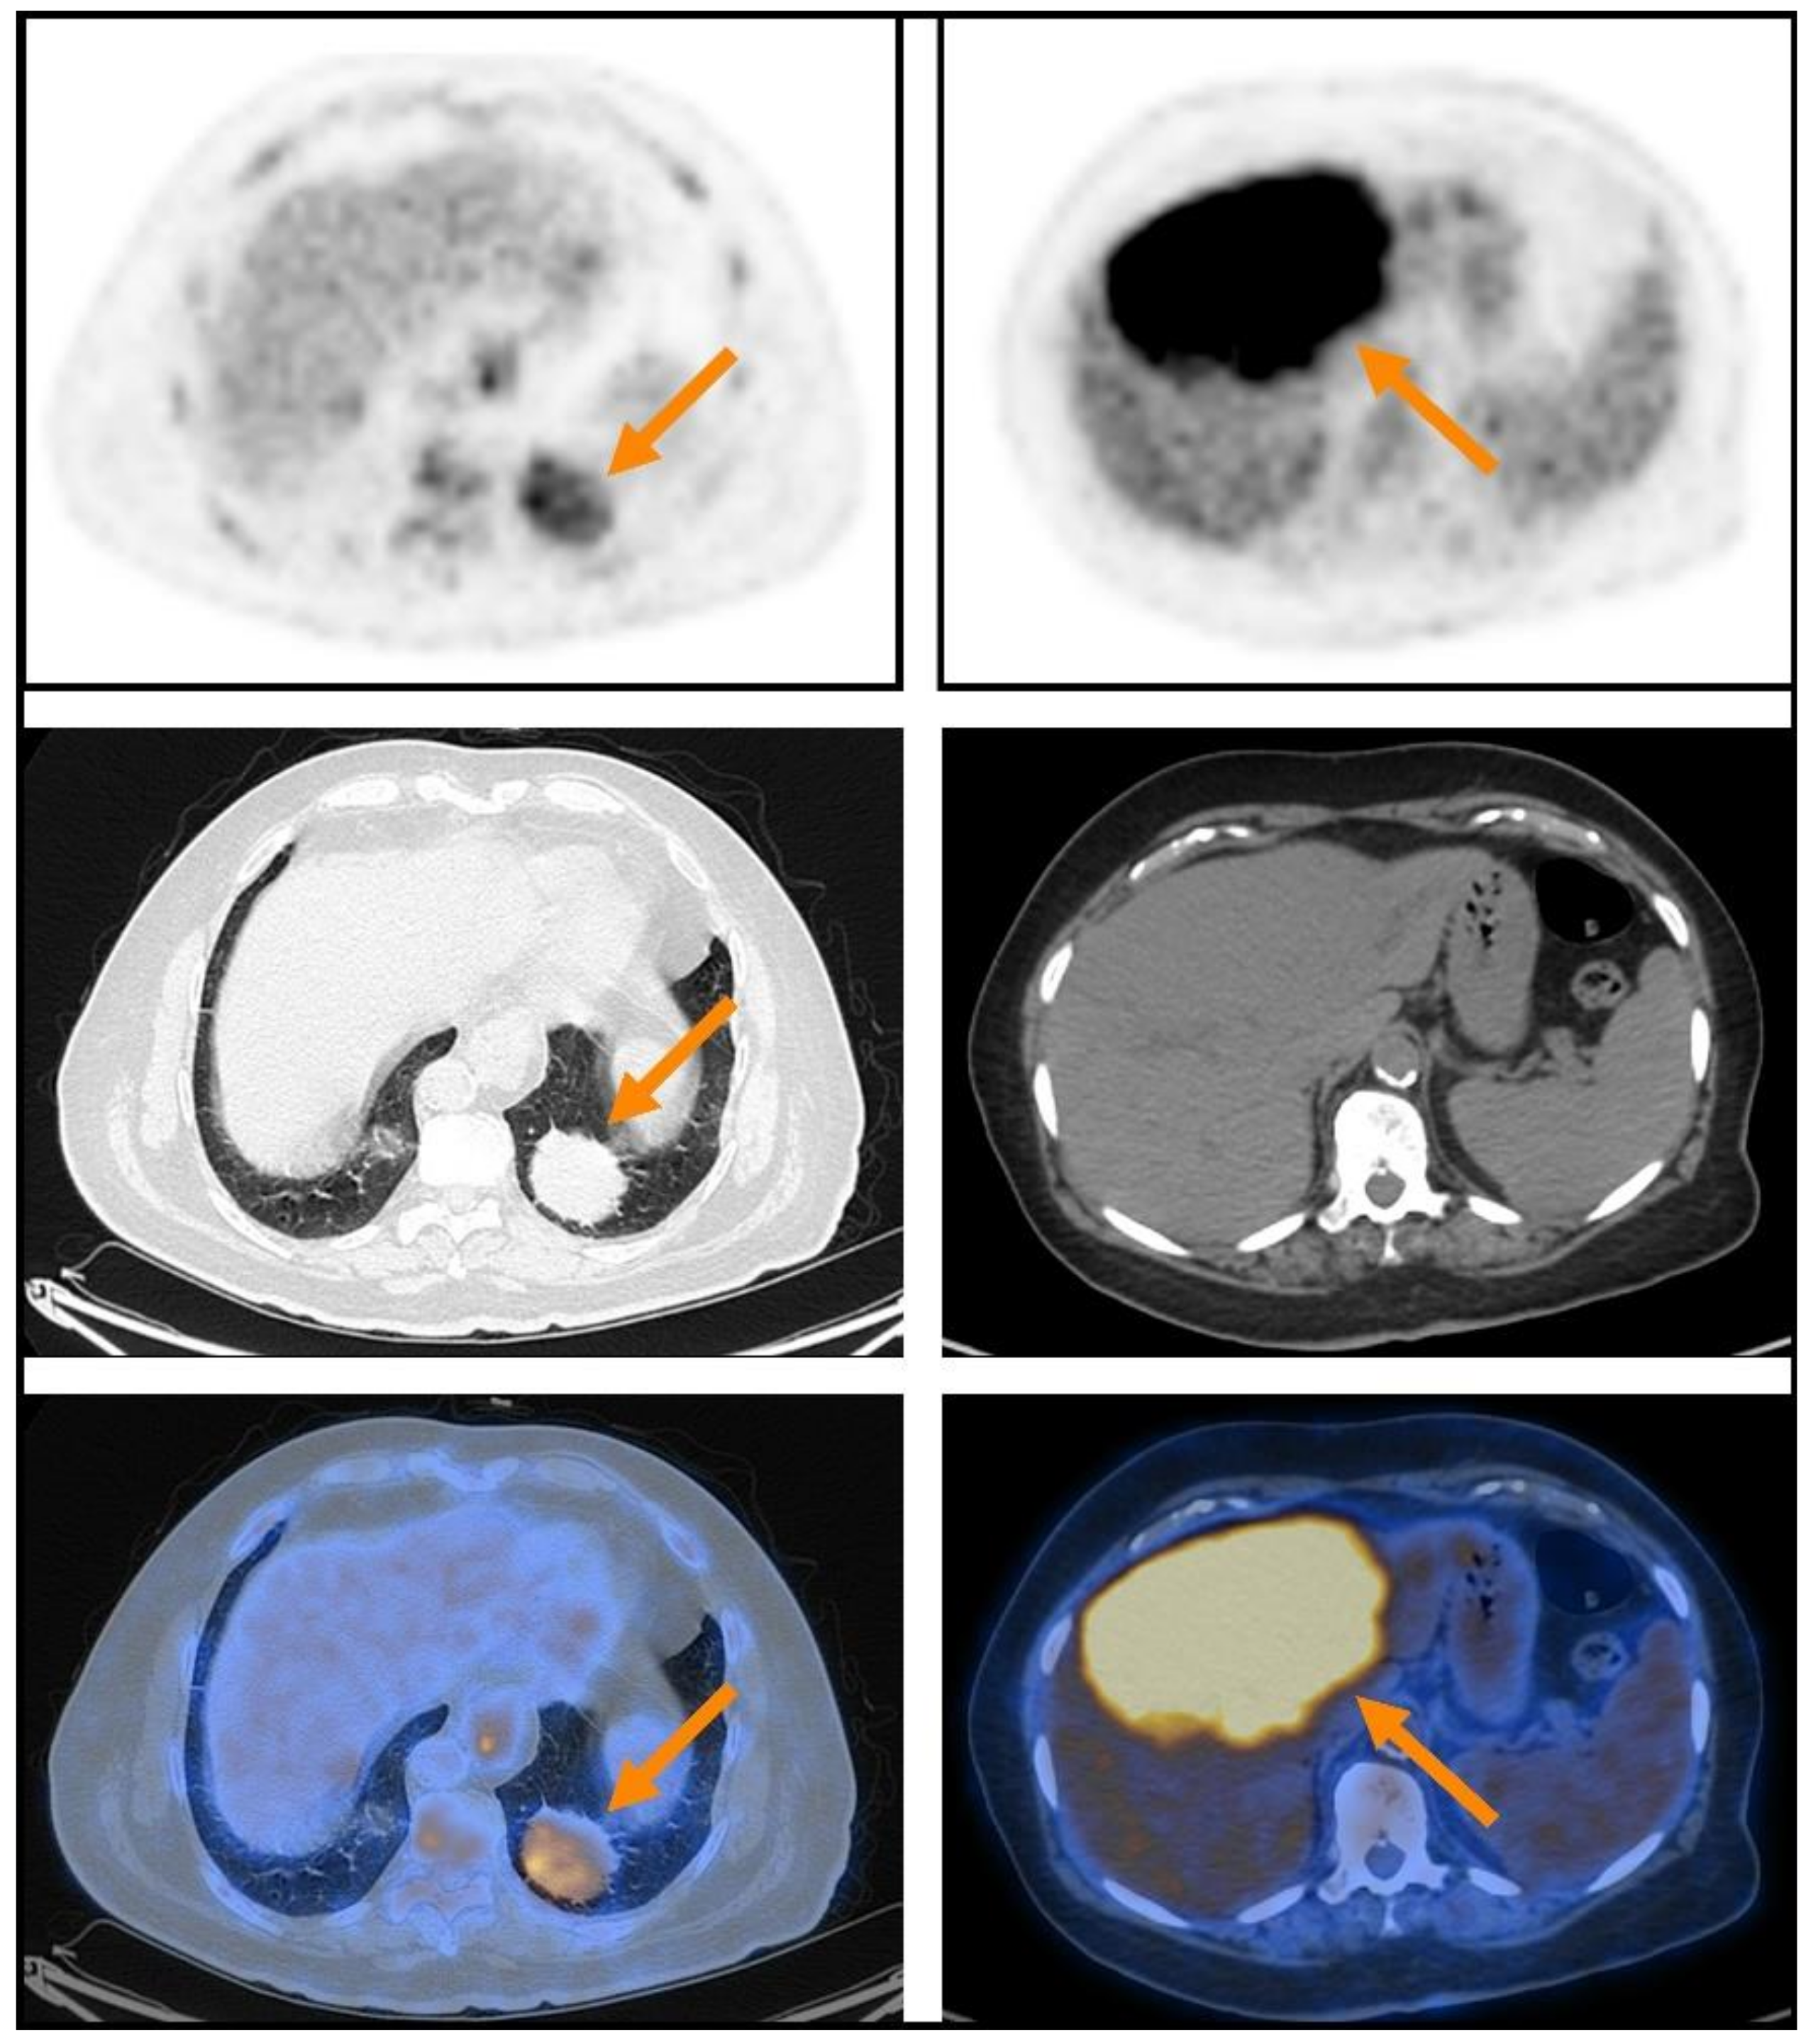

| Lung | 6/66 (9.1%) | |

- Albano, D.; Borghesi, A.; Bosio, G.; Bertoli, M.; Maroldi, R.; Giubbini, R.; Bertagna, F. Pulmonary mucosa-associated lymphoid tissue lymphoma: 18F-FDG PET/CT and CT findings in 28 patients. Br. J. Radiol. 2017, 90, 20170311. [Google Scholar] [CrossRef]